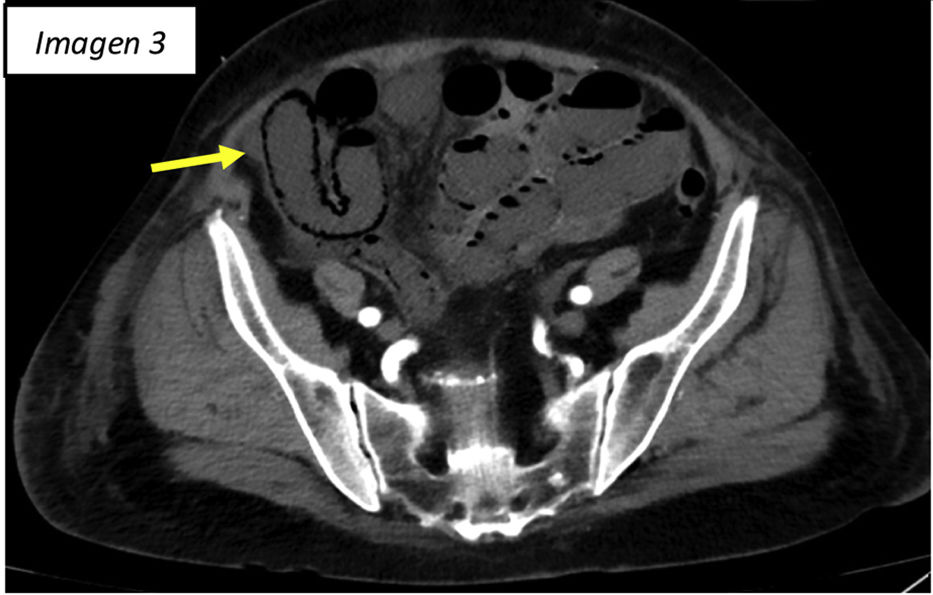

Isquemia mesentérica

Mesenteric ischemia